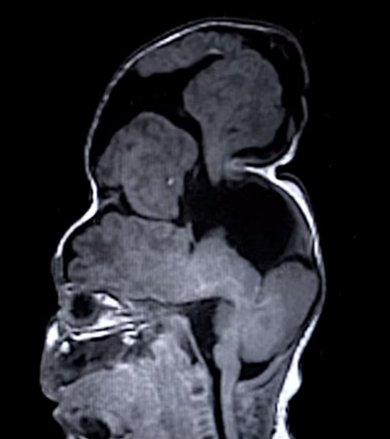

Bentley Yoder出生的时候,他的大脑就长在颅骨外。医生说他不可能活下来,但他现在却活得很好。现7个月的他已经历修复外科手术,将他的大脑移回颅骨内。

Bentley的父母Sierra和Dustin均25岁,当他们在妊娠22周做常规超声波检查的时候,发现某些事情不对劲。仍在子宫内的Bentley被诊断患有脑膨出,即他的大脑组织从颅骨缺损口向外膨出。这对父母被告知他们的孩子出生后可能活不了很久,他的大脑也不会具备任何功能。

虽然Bentley的大脑组织有很大一部分长到了颅骨外,但他出生后能够正常发育,他饿了的时候也会哭。医生对此表示质疑,坚称Bentley头顶的东西只是“坏死的组织”,它不可能有任何功能,但Bentley的行为和正常发育表明情况并非如此。

于是他们找到了波士顿儿童医院的John Meara医生,他的医疗团队每年都要接手许多严重的脑膨出病人。医生们仔细检查过Bentley之后,发现他那长出来了的大脑组织不能被切除,因为它们负责控制行动、解决问题和视力等功能。这些大脑组织必须被塞回颅骨。

医生们利用3D打印的模型开始他们的计划。Bentley颅骨外的大脑组织体积为100立方厘米,因此医生们必须扩大他的颅骨以便容纳这些组织。在手术前,Meara利用塑料模型进行过估算,看他的团队能将多少Bentley的大脑组织塞回颅骨。

5月24日,手术开始了。医生们特意选在这一日是因为Bentley的颅骨已经足够坚硬,能够经受手术;再晚一点他那些大脑组织可能会破裂。手术前列步是排干Bentley大脑中的脑脊液,接着外科医师需切开他的颅骨,并轻轻地将脑组织塞进去。在此过程中余下的骨头将被用来合拢颅骨缝隙。整个过程历时六个小时,手术非常顺利,不过Bentley后续还要经历一些手术,排出大脑中多余的脑脊液。